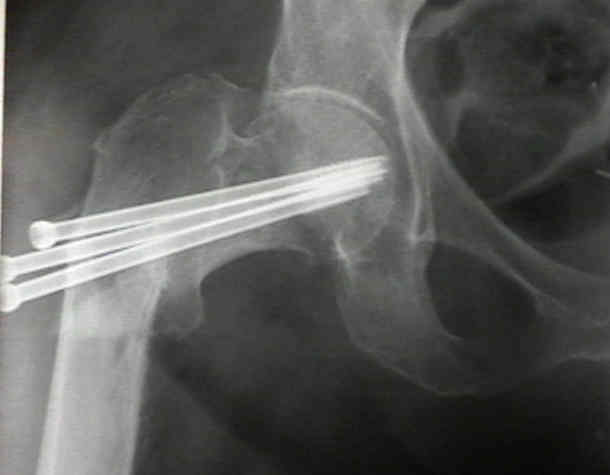

Trauma implant Cannulated Screw orthopedic implant,Cannulated Titanium Alloy Bone locking Screws,Medical Bone Screws

Durable 4.0 Mm Cannulated Screw Corrosion Resistant 20 - 68 Mm Length Images |